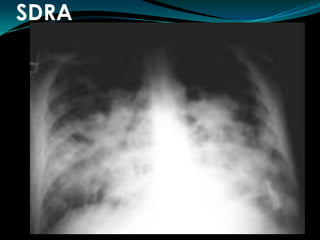

SDRACriterios de DiagnósticoINICIO AGUDOINFILTRADOS BILATERALES RXPRESION CAPILAR PULMONAR < 18 mm Hg.No signos  clínicos de ICCPaO2 / FIO2 < 200

SDRACriterios de DiagnósticoINICIOAGUDOINFILTRADOS BILATERALES RXPRESION CAPILAR PULMONAR < 18 mm Hg.No signos clínicos de ICCPaO2 / FIO2 < 200